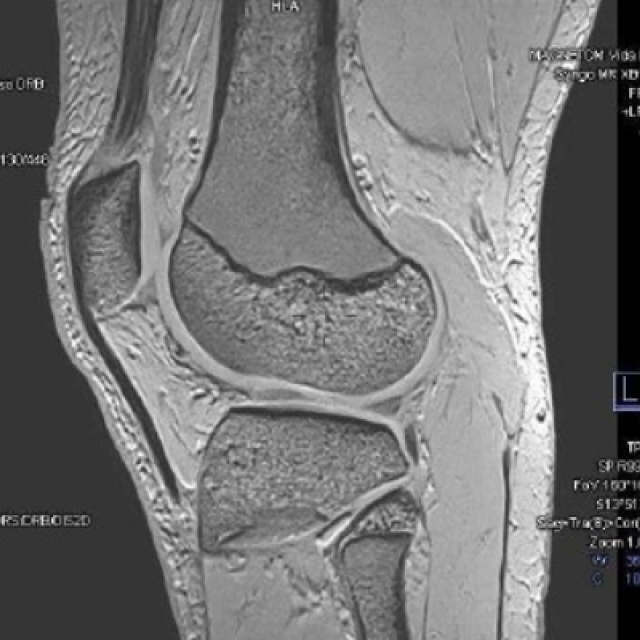

Canopy news Latest news and info from Canopy Healthcare December 01 2025 Canopy Imaging Brings Cutting-Edge, Sustainable MRI Technology to Ormiston MRI Canopy Imaging is proud to announce the installation of the MAGNETOM Vida Fit, a state-of-the-art 3T MRI system from Siemens Healthineers, at its Ormiston Canopy Imaging Clinic in Auckland. Read more October 23 2025 Canopy Healthcare Achieves Toitū Carbonreduce Certification Toitu We’re proud to share that Canopy Healthcare has received Toitū carbonreduce certification. This a major milestone in our sustainability journey and one that we are all very proud of. Read more September 09 2025 Canopy Imaging Opens New State-of-the-Art Clinic in Ahuriri Ahuriri Canopy Healthcare is proud to announce the opening of its newest Canopy Imaging clinic in the heart of Ahuriri, bringing advanced diagnostic imaging services closer to the communities of Napier and surrounding areas. Read more September 02 2025 Bringing World-Class Cancer Care and Imaging Under One Roof in Hawke’s Bay Canopy Healthcare has opened its first co-located cancer care and diagnostic imaging clinics at Kaweka Hospital, Hastings, bringing world-class integrated healthcare closer to home for the Hawke’s Bay community. Read more July 08 2025 What to expect from your pregnancy ultrasound scan Pregnancy Ultrasound An ultrasound scan is a very safe procedure that uses high-frequency sound waves to make and record images of your baby while you are pregnant. Ultrasound scans are an important part of pregnancy care. Read more June 23 2025 Bowel Cancer Awareness Month: Screening with a CT Colonography CT Colonography If you are considering bowel cancer screening or have been referred for further investigation, you may be offered a test called CT colonography. Read more May 21 2025 Understanding Pelvic Floor Disorders and how Canopy Imaging can help MRI Pelvic Floor Pelvic floor disorders affect up to 25% of women. They often present with incontinence, organ prolapse, and difficulty defaecating (passing stools). Read more May 14 2025 A Non-Invasive Look at Your Heart Arteries - CT Coronary Angiography CT Coronary Angiography What is CT Coronary Angiography? Read more May 06 2025 Caring for your breast health Breast Imaging Canopy Imaging Mammogram Looking after your breast health is one of the most important things you can do for yourself. Read more April 29 2025 A Quick Scan for Stronger Bones Bone Density DEXA As we get older, our bones naturally get thinner (less dense) and weaker. In osteoporosis, this bone loss happens faster and is severe enough to make bones fragile and more likely to fracture (break), even from a minor bump or fall. Read more April 15 2025 Your MRI Experience at Canopy Imaging MRI We understand that undergoing your first MRI scan can be an unfamiliar and potentially unsettling experience. Read more April 01 2025 Heart Health Check - A simple scan that could save your life CT CT Calcium Score When it comes to your heart, early detection of potential issues is key. One of the most effective ways to assess your heart health is through a CT Calcium Score. Read more Load more